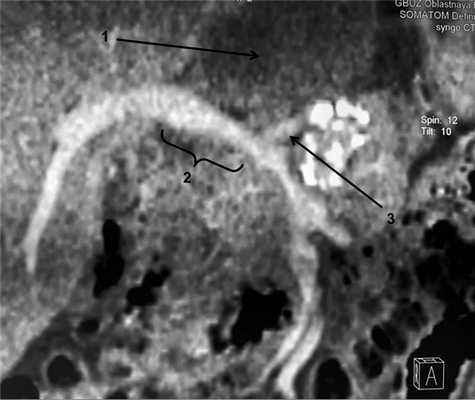

В артериальной фазе левая печеночная артерия не визуализируется, правая контрастируется на всем протяжении, с паразитом не контактирует (рис. 3). Рис. 3. МСКТ-ангиограмма брюшной полости (венозная фаза). 1 — патологический очаг в левой доле печени, 2 — фрагмент правой ветви воротной вены, 3 — устье левой ветви воротной вены.

В венозную фазу левая ветвь воротной вены прослеживается в начальном сегменте, в области бифуркации, далее вовлечена в патологический процесс. Также выявлен фрагмент правой ветви воротной вены, плотно прилежащий к паразиту (рис. 4). Рис. 4. МСКТ-ангиограммы брюшной полости (венозная фаза). 1 — правая печеночная вена, 2 — срединная печеночная вена.